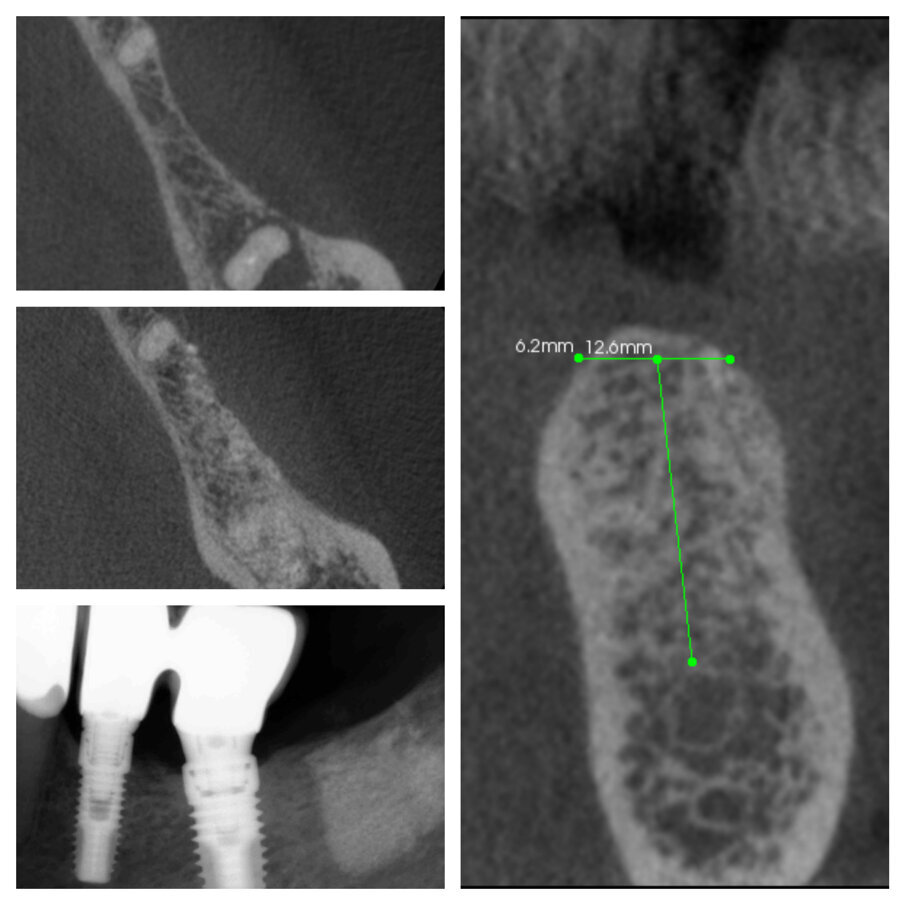

Fig. 2c_CBCT pre e post intervento a 6 mesi.

Fig. 3c_CBCT pre intervento e dopo 6 mesi a confronto.